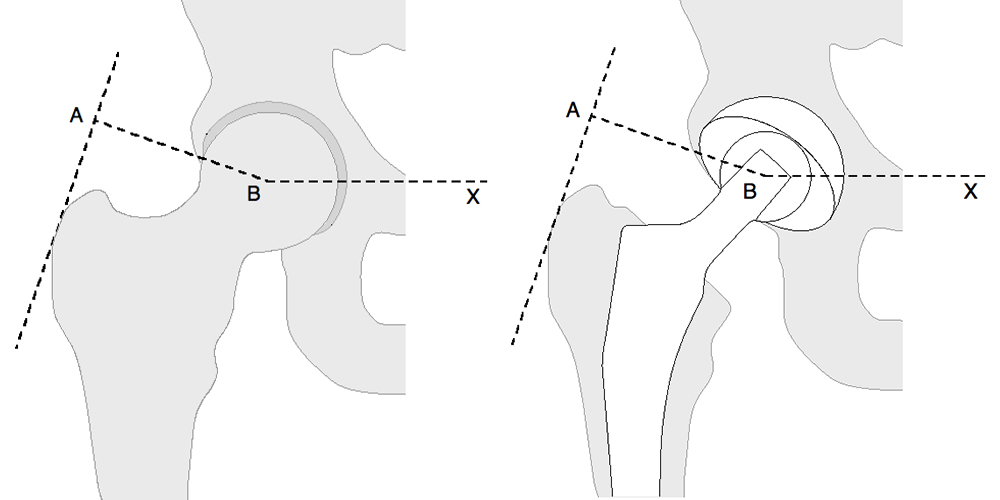

A musculatura abdutora, atuando sobre um braço de alavanca que se estende da face lateral do grande trocânter ao centro da cabeça femoral, tem que exercer um momento igual para manter a pelve na horizontal quando em apoio sobre uma perna somente (2,5x peso corporal) e um momento maior ainda para inclinar a pelve para o mesmo lado quando em marcha ou correndo. A carga sobre a cabeça femoral é em torno de 3,5 a 5x o peso corporal em marcha e pode atingir até 10x ao correr ou saltar. O posicionamento cirúrgico pode alterar estes braços de alavanca através da modificação de offsets e osteotomias do grande trocânter e sua posterior fixação (Fig. .4) (2,7).

A reconstrução ideal do quadril reproduz o centro normal de rotação da cabeça femoral, sendo esta determinada pela altura vertical (offset vertical), offset horizontal (ou simplesmente offset) e a anteversão do colo femoral (offset anterior)(Fig. .5). O offset vertical e horizontal aumentam com o alongamento do colo da haste femoral. O comprimento do colo pode ser modificado através do uso de cabeças femorais modulares que se encaixam em um cone Morse no colo da haste. A haste com colo variável oferece uma oportunidade para correção da altura vertical da cabeça, que pode ser medida, por exemplo, entre o centro da cabeça e o trocânter menor. Um offset horizontal restaurado inadequadamente para menor pode resultar em aumento da força necessária da musculatura abdutora, acarretando em claudicação, impacto ósseo e luxação. O inverso causa aumento de tensões na haste e no manto de cimento, com possível fratura ou soltura da haste (2,4,7).